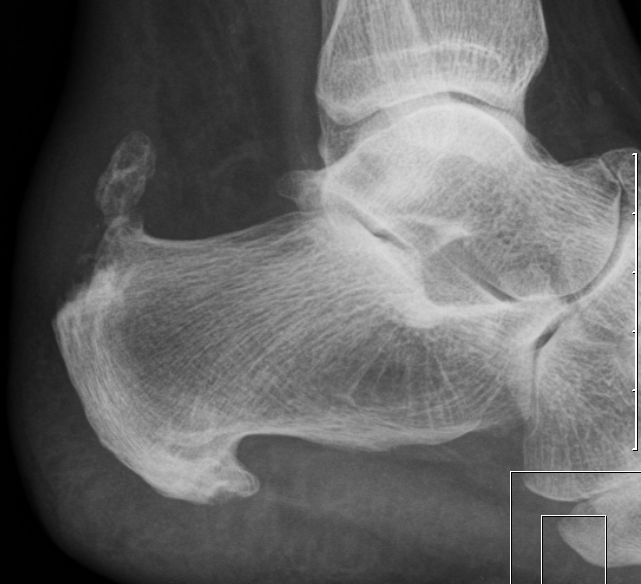

| Röntgenbild | plantarer Fersensporn |

![]() |

||||